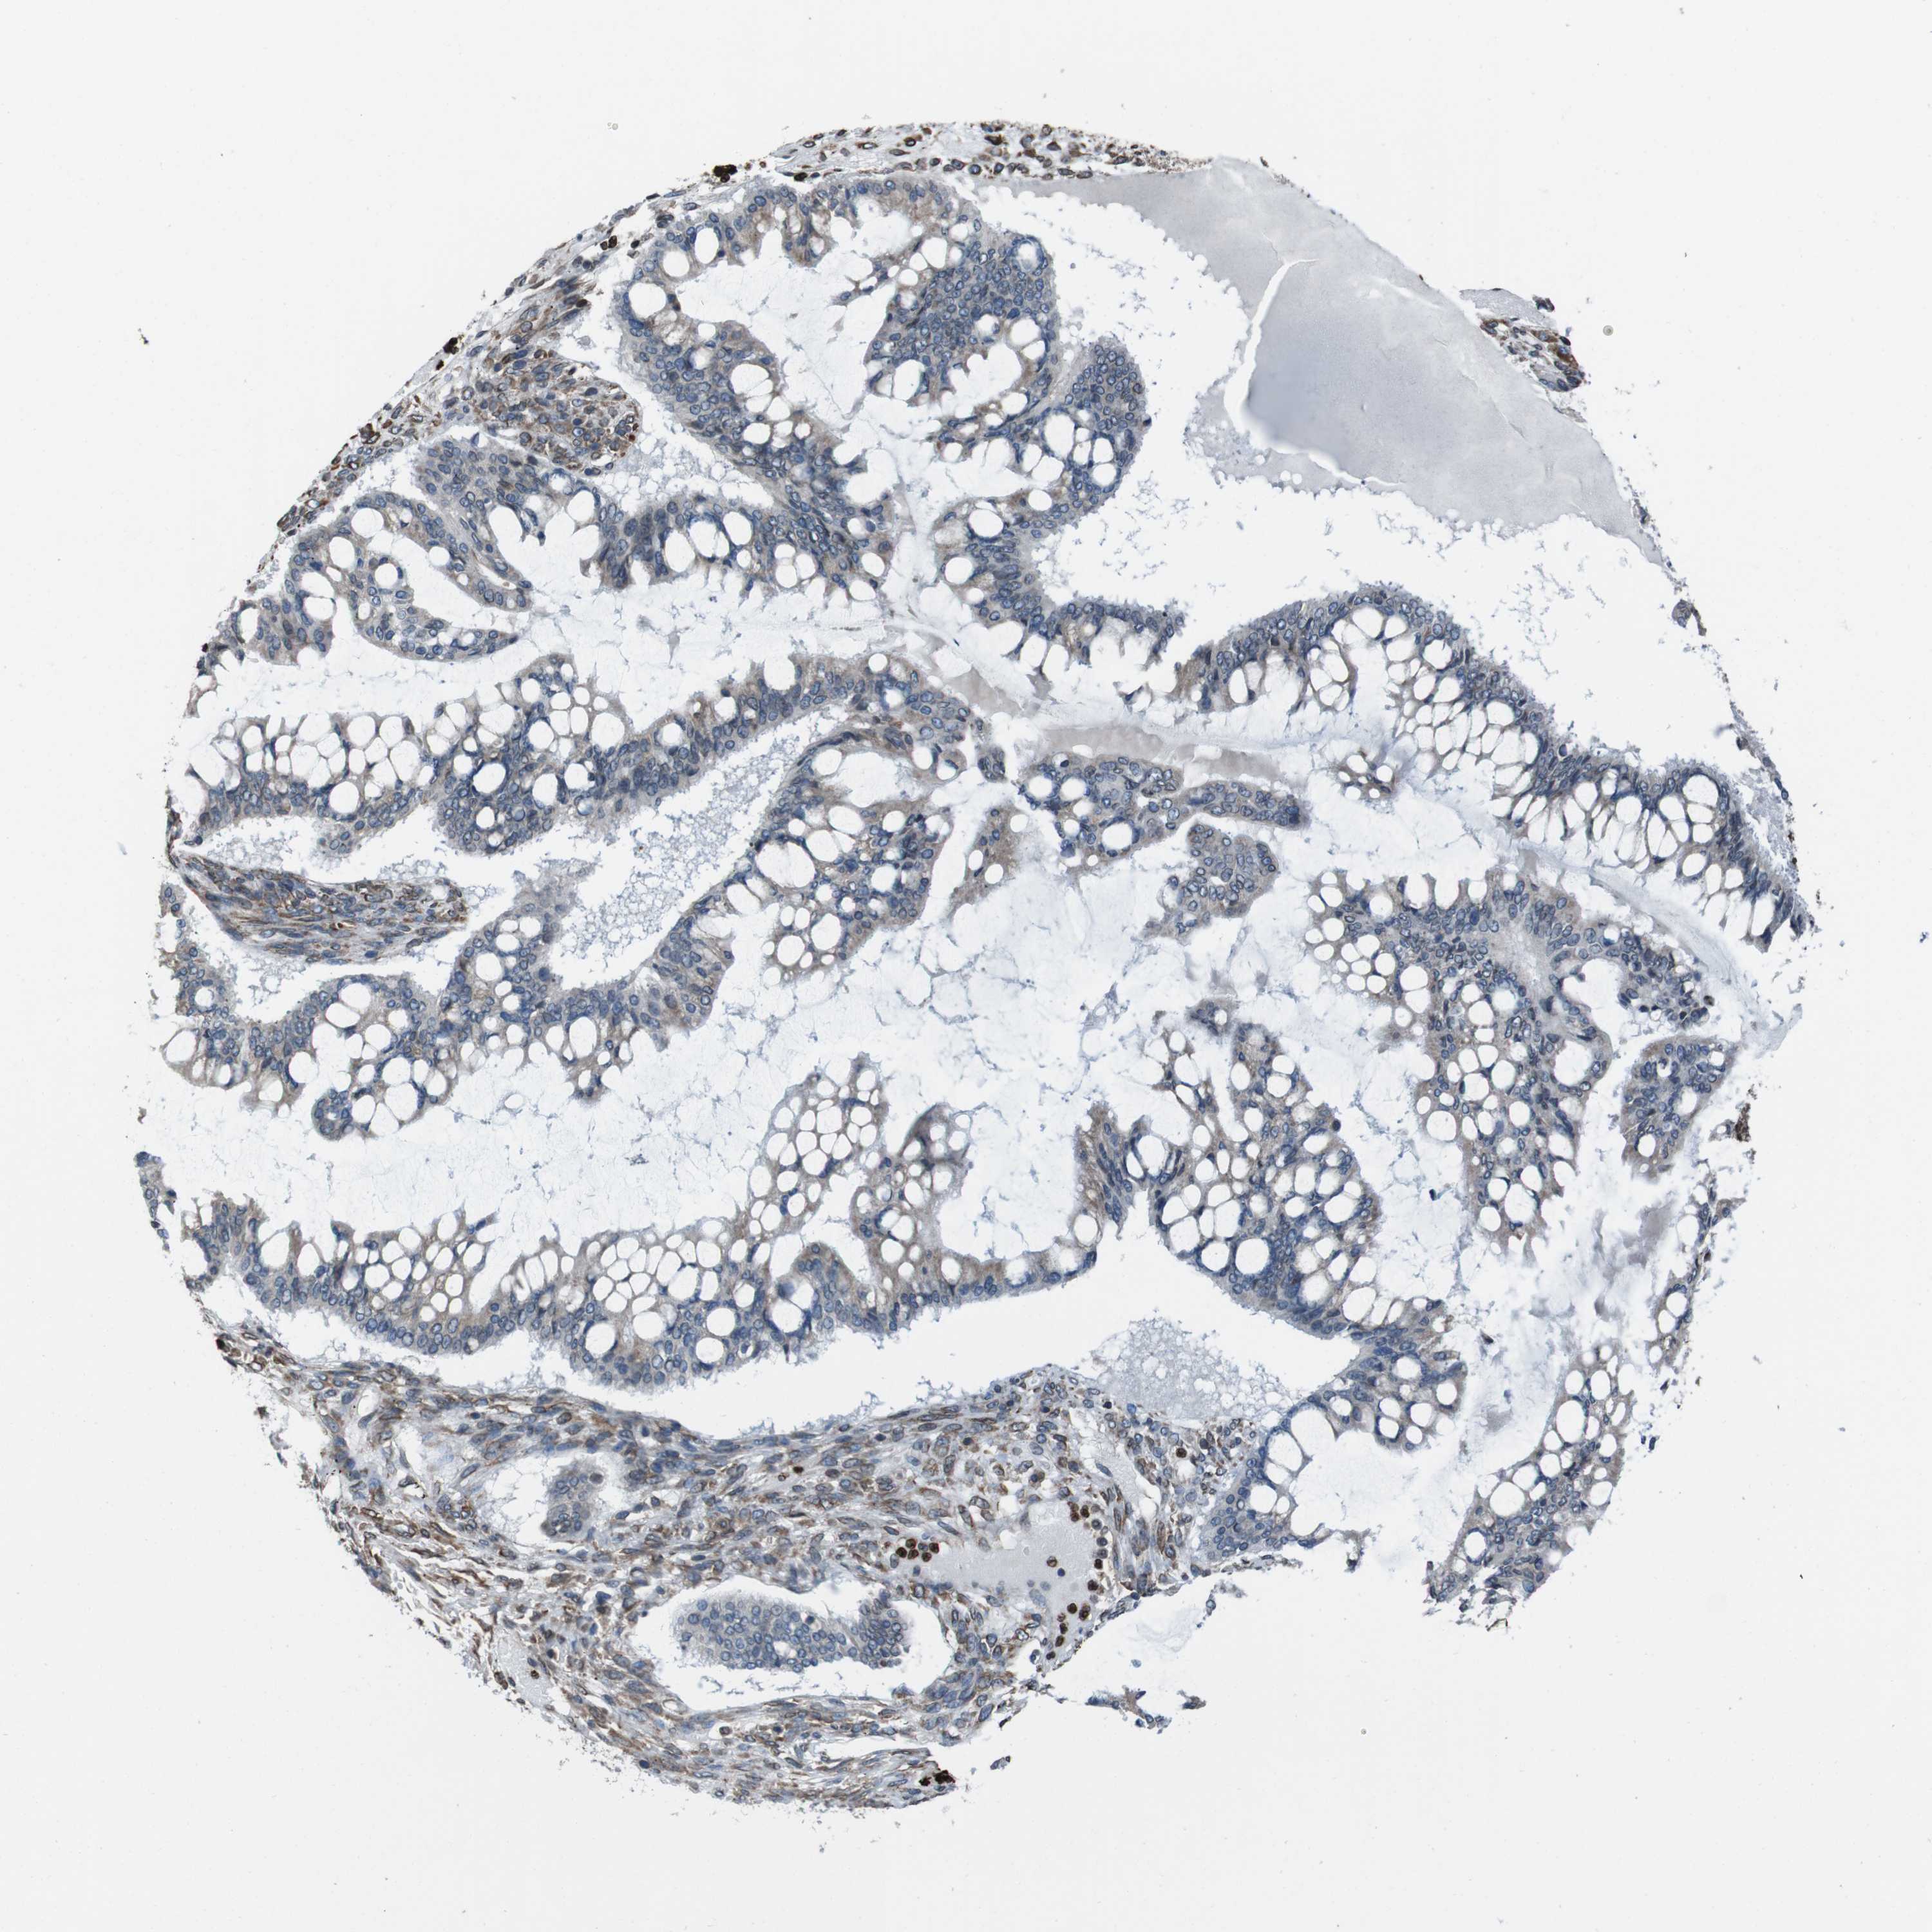

OVARIAN CANCER - Protein expressioni

A mouse-over function shows sample information and annotation data. Click on an image to view it in a full screen mode. Samples can be filtered based on level of antibody staining by selecting one or several of the following categories: high, medium, low and not detected. The assay and annotation is described here.

Note that samples used for immunohistochemistry by the Human Protein Atlas do not correspond to samples in the TCGA dataset.

Antibody stainingi

Antibody staining in the annotated cell types in the current human tissue is reported as not detected, low, medium, or high, based on conventional immunohistochemistry profiling in selected tissues. This score is based on the combination of the staining intensity and fraction of stained cells.

Each image is clickable and will lead to virtual microscopy that enables deeper exploration of all samples and also displays staining intensity scores, fraction scores and subcellular localization as well as patient and tissue information for each sample.

Antibody HPA012863

Staining

High

Medium

Low

Not detected

Intensity

Strong

Moderate

Weak

Negative

Quantity

>75%

75%-25%

<25%

None

Location

Nuclear

Cytoplasmic/membranous

Cytoplasmic/membranous,nuclear

Cystadenocarcinoma, serous, NOS

Carcinoma, endometroid

Cystadenocarcinoma, mucinous, NOS

Carcinoma, NOS